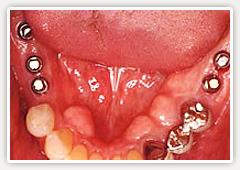

【術後】

左右奥をインプラントで治療しました。(左2本、右3本)

【術後経過】

取り外しでなく固定になり、退職後の唯一の愉しみの食事も美味しくいただけるようになったそうです。義歯の煩わしさもなく快適です。